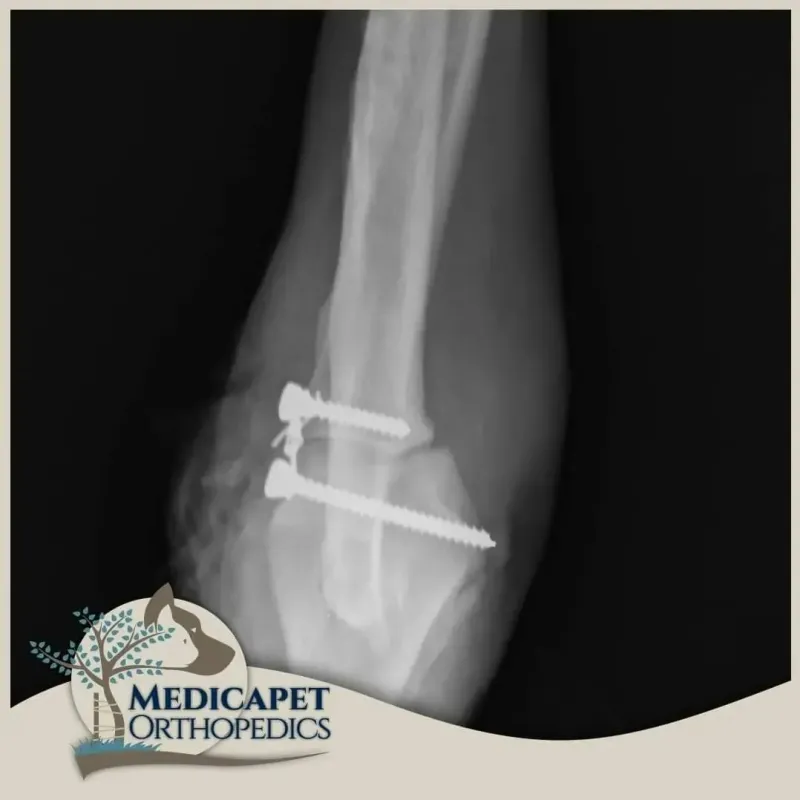

Dirseği saran bağlar ve eklem kapsülünün ağır hasarlı olmadığı durumlarda ameliyatsız kapalı redüksiyon yoluna gidebiliyoruz. Bu tip bir tedavi kısa vadeli etkin takip gerektirir. Dirseğin tekrar çıkması halinde muhtemelen cerrahi tedaviye karar verilecektir. Bağ hasarının yüksek olduğu durumlarda dirsek çıkığının tedavisi açık ameliyat ile yapılır ve hasar gören bağları taklit eden tel, vida ve sentetik bağlardan faydalanırız. Cerrahınız dirsek çıkığının şekline

göre, tedavi seçeneklerini hastanın maksimum faydasına göre değerlendirecektir.